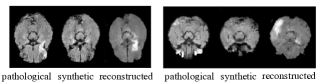

Refer to caption

Figure 2: CycleGAN failure cases caused by the one-to-many problem. Each subfigure from left to right shows the input, the pseudo healthy and the input reconstruction. The lesion location in the reconstruction differs from the original one, since an accurate pseudo healthy image has no information to guide the reconstruction process. Images taken from ISLES.